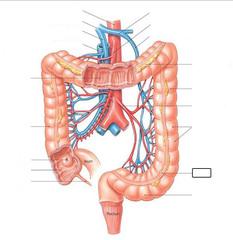

Ascending/transverse/descending/sigmoid colon

Cecum

Duodenum

Gall bladder

Hepatic portal vein

Ileum

Jejunum

Liver

Mesentery

Pancreas

Rectum

Splenic artery/vein

Superior/inferior mesenteric artery

Vermiform appendix